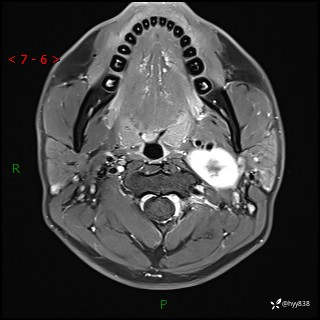

现病史:患者约3年前因感冒发现左侧颈部长一肿物,约半个鸡蛋大小,无明显疼痛及其他不适,一直未行特殊处理。3个月前发现左侧颈部肿物变大,随后至当地市第二人民医院耳鼻喉科行左侧颈部彩超示:左侧颈部囊实混合性包块;喉部MPR示:左侧胸锁乳突肌内前方占位,累及左侧喉旁间隙,建议增强扫描。建议手术治疗。患者考虑。随后至我院肿瘤科就诊,行细胞学穿刺示:考虑血管源性肿瘤可能,建议进一步检查。建议至我院口腔科就诊,行颌面部MRI示:左侧颌下腺后方团状异常信号灶,建议增强。建议手术治疗。为求进一步治疗,门诊以“左侧颈部肿物”收入院。 起病以来,患者神志清、精神良好,饮食睡眠良好,大小便正常,体重未见明显变化。

颈部MRI平扫+增强